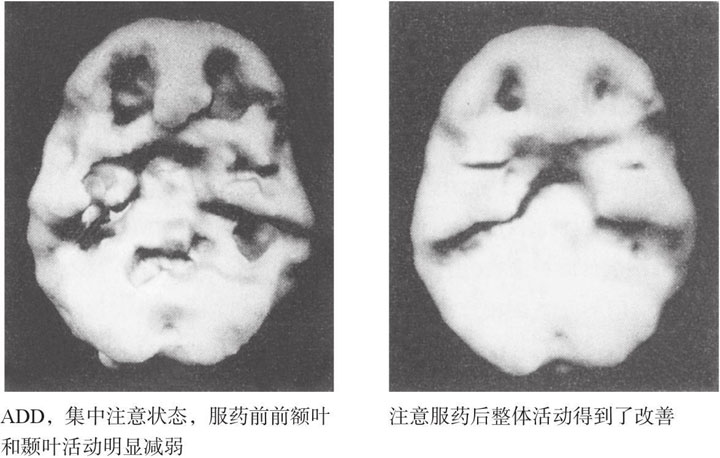

本书的目的并不是要读者们去医院做一次脑成像扫描。你不需要脑扫描就能从本书中获益。实际上,我写作本书的目的是通过展示脑成像结果,从更广阔的视野解释人类的行为,包括各种异常和正常的行为。通过这些脑成像结果,我们可以发现,很多在过去一直被认为是精神病性质的问题——比如抑郁、惊恐障碍、注意力缺陷障碍等,实际上都是一些生理学问题,并可以结合传统的心理学和社会学方法通过药物进行治疗。